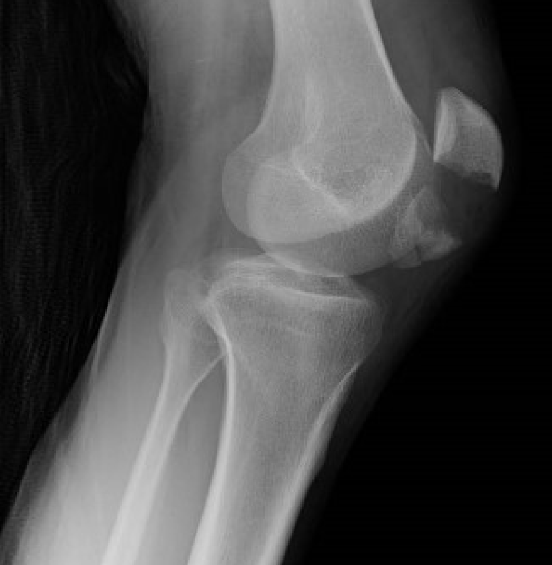

◇膝蓋骨骨折

・ 大腿四頭筋力は骨折線を離開させるのか?

◇脛骨高原骨折

・ 術前評価は何をすれば良いのか?

・ 術後荷重スケジュール

・ 後療法のポイントは?

・ 歩行時痛への対応は?

◇ 画像の読影

・遠位脛腓靭帯損傷

・ 三角靭帯損傷